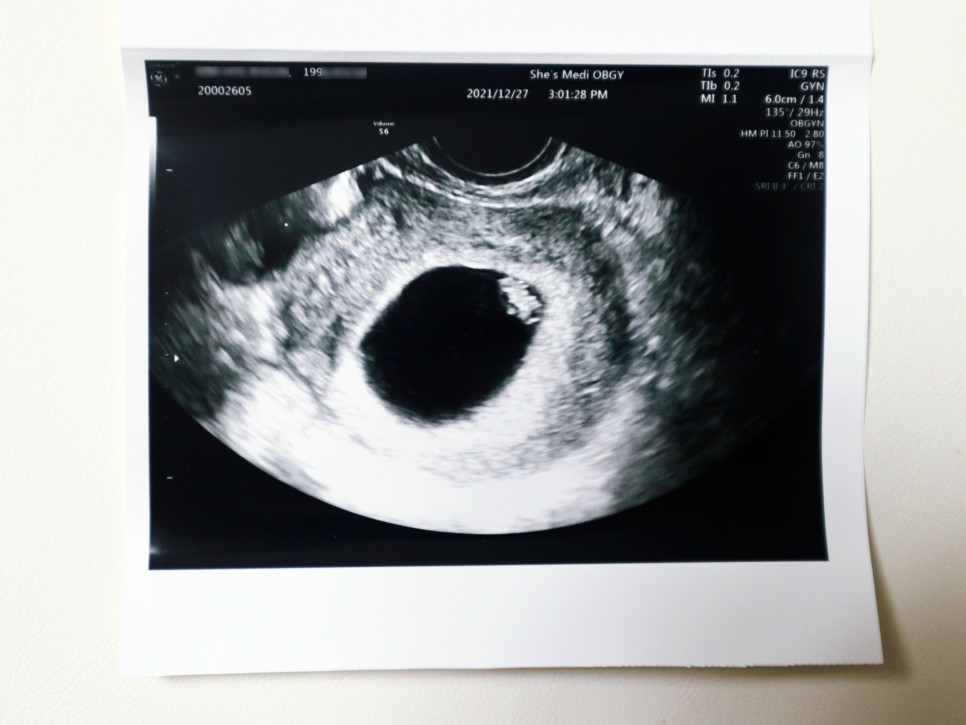

임신 7주 0일(21년 12월 27일) 임신 7주차 태아 심박수 태아 소견 신장 0.9cm

임신 4주 5일 첫 방문 때 0.2cm 아기집을 봤는데 정작 태아는 보지 못했어요.그래서 이날은 아기 집에 두루치를 확인하고 심박수를 체크하는 날이었어요.임신 7주 차 초음파상 아기의 집도 매우 커지고 있었는데, 그 안에서 젤리 아기를 발견할 수 있었습니다. 노른자도 꼭 확인했어요.선생님이 보시면 넓은곳이 많은데 저위에 붙어있다고 ㅋㅋㅋㅋ

임신 초기에 엽산과 비타민D를 잘 먹으라는 말씀과 소량의 피의 비침은 괜찮지만 생리혈처럼 쏟아져 나오는 증상이 있으면 바로 내원하라고 말씀하셨습니다.아기 심장 박동수도 굿굿!!!